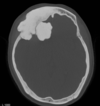

Osteoma Osteóide - A TC mostra o nidus radioluscente, cercado por reação esclerótica e , as vezes, pode mostrar um ponto esclerótico dentro do nidus.

Predomina 10 - 30 anos.

Nicho radiotransparente < 1cm circundado por reação esclerótica. Localização cortical / justacortical em ossos longos: femur proximal e tibia.

Clinica tipica: dor mais intensa a noite aliviada por AAS.

Quando nidus > 2cm = osteoblastoma. TC é a modalidade de escolha (RM pode não ver o nidus).